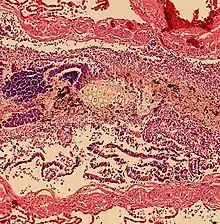

Pulmonary aspiration of particulate matter may result in acute airway obstruction which may rapidly lead to death from arterial hypoxemia.[2]

Pulmonary aspiration of acidic material (such as stomach acid) may produce an immediate primary injury caused by the chemical reaction of acid with lung parenchyma, and a later secondary injury as a result of the subsequent inflammatory response.[2]

Pulmonary aspiration may be followed by bacterial pneumonia. Community-acquired aspiration pneumonia is usually caused by anaerobic bacteria, whereas hospital-acquired aspiration pneumonia is more often caused by mixed flora, including both aerobic and anaerobic bacteria.[2]